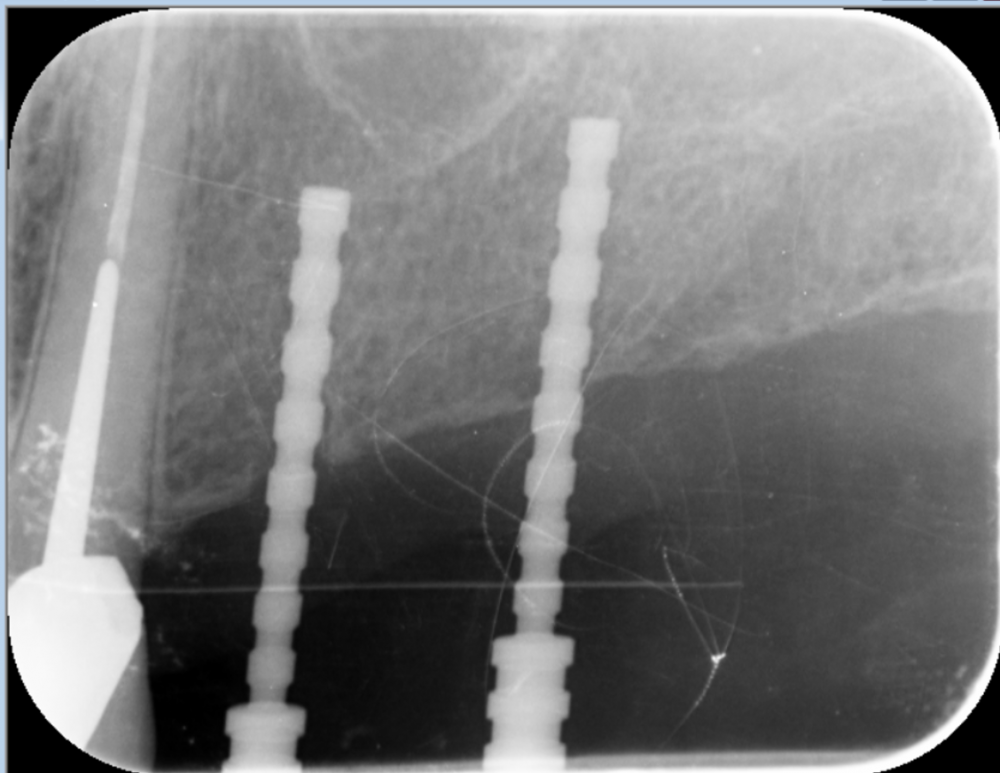

Dr T Опубликовано 13 мая, 2023 Поделиться Опубликовано 13 мая, 2023 (изменено) Уважаемые стоматологи, прокомментируйте, пожалуйста, что можно порекомендовать в данной ситуации доктору нашей клиники. Предполагался мост на имплантатах зубы 24-26, мужчина, 45 лет. Доктор выбрал 2 имплантата 4.2 по 8мм. Кость по КТ хорошая, но в ходе имплантации что-то пошло не так. В конечном итоге, один имплантат стал близко к зубу и то со второго раза и подсыпалась косточка. Можно ли оставлять как есть или слишком близко к зубу и что делать? Имплантация была 2 недели назад. На снимках первая установка и потом после попытки выпрямить 24 имплантат. Изменено 13 мая, 2023 пользователем Dr T Ссылка на комментарий

Dr T Опубликовано 13 мая, 2023 Автор Поделиться Опубликовано 13 мая, 2023 @Женька Да, без позиционера. Первый из последних двух снимков был сделан в день имплантации, а последний - через 2 недели. Ссылка на комментарий

Irouil Опубликовано 14 мая, 2023 Поделиться Опубликовано 14 мая, 2023 (изменено) @Dr T рентген на данный момент выглядит хорошо, он показанием для удаления импланта точно не является, хотя протезирование потребуется очень грамотное (даже просто установка формирователей должна быть проведена грамотно, обязательно с учётом остаточной высоты апроксимального гребня, надо не напортачить с разрезами и швами, в общем - планировать надо будет точнее, чем перед имплантацией). Но важно наблюдать за симптоматикой зуба, если появятся признаки реактивного периодонтита - дать гормоны на 3-6 дней, чтобы сбить отёки и предупредить необратимые изменения, если резкой положительной динамики не будет - винт на выход. Помните, что ПО АКАДЕМИЧЕСКИМ МЕРКАМ этот имплант ФОРМАЛЬНО установлен неправильно Изменено 14 мая, 2023 пользователем Irouil Ссылка на комментарий